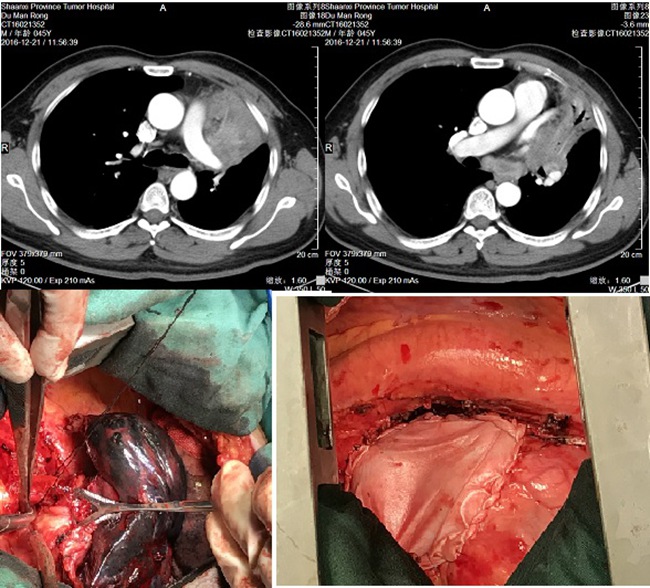

患者杜某,男性,45岁,因“咳嗽2月”慕名找到了素股胸外科主任雷光焰教授,入院完善各项检查后,确诊为左肺上叶鳞癌(中央型,分期cT4N2M0)。雷教授分析病情后认为:患者年轻,肺功能良好,左肺上叶病变范围大,与左肺动脉及左上肺静脉关系密切,但无远处转移,仍有手术完全切除可能,建议行术前新辅助化疗,以期提高手术切除率。但经过两周期的新辅助治疗后,患者左肺上叶病变未见明显缩小,手术难度依然很大。

鉴于患者及家属强烈的手术意愿,经全科术前讨论,与患者家属充分沟通后,于2016年12月27日在雷主任带领的胸外二病区治疗团队为这位年轻的患者施行了左全肺扩大切除+心包修补术。手术中先行清扫了肺门及隆突下多枚肿大融合淋巴结,单个直径达3cm,才使肺动脉干便于显露,由于病变包绕左上肺静脉,与心包融合,切开心包,经心包内游离左肺上叶静脉,紧贴心房离断缝合,整块切除肿瘤,心包缺损范围达10×8cm,以补片修补心包。手术过程顺利,术后10天康复出院。